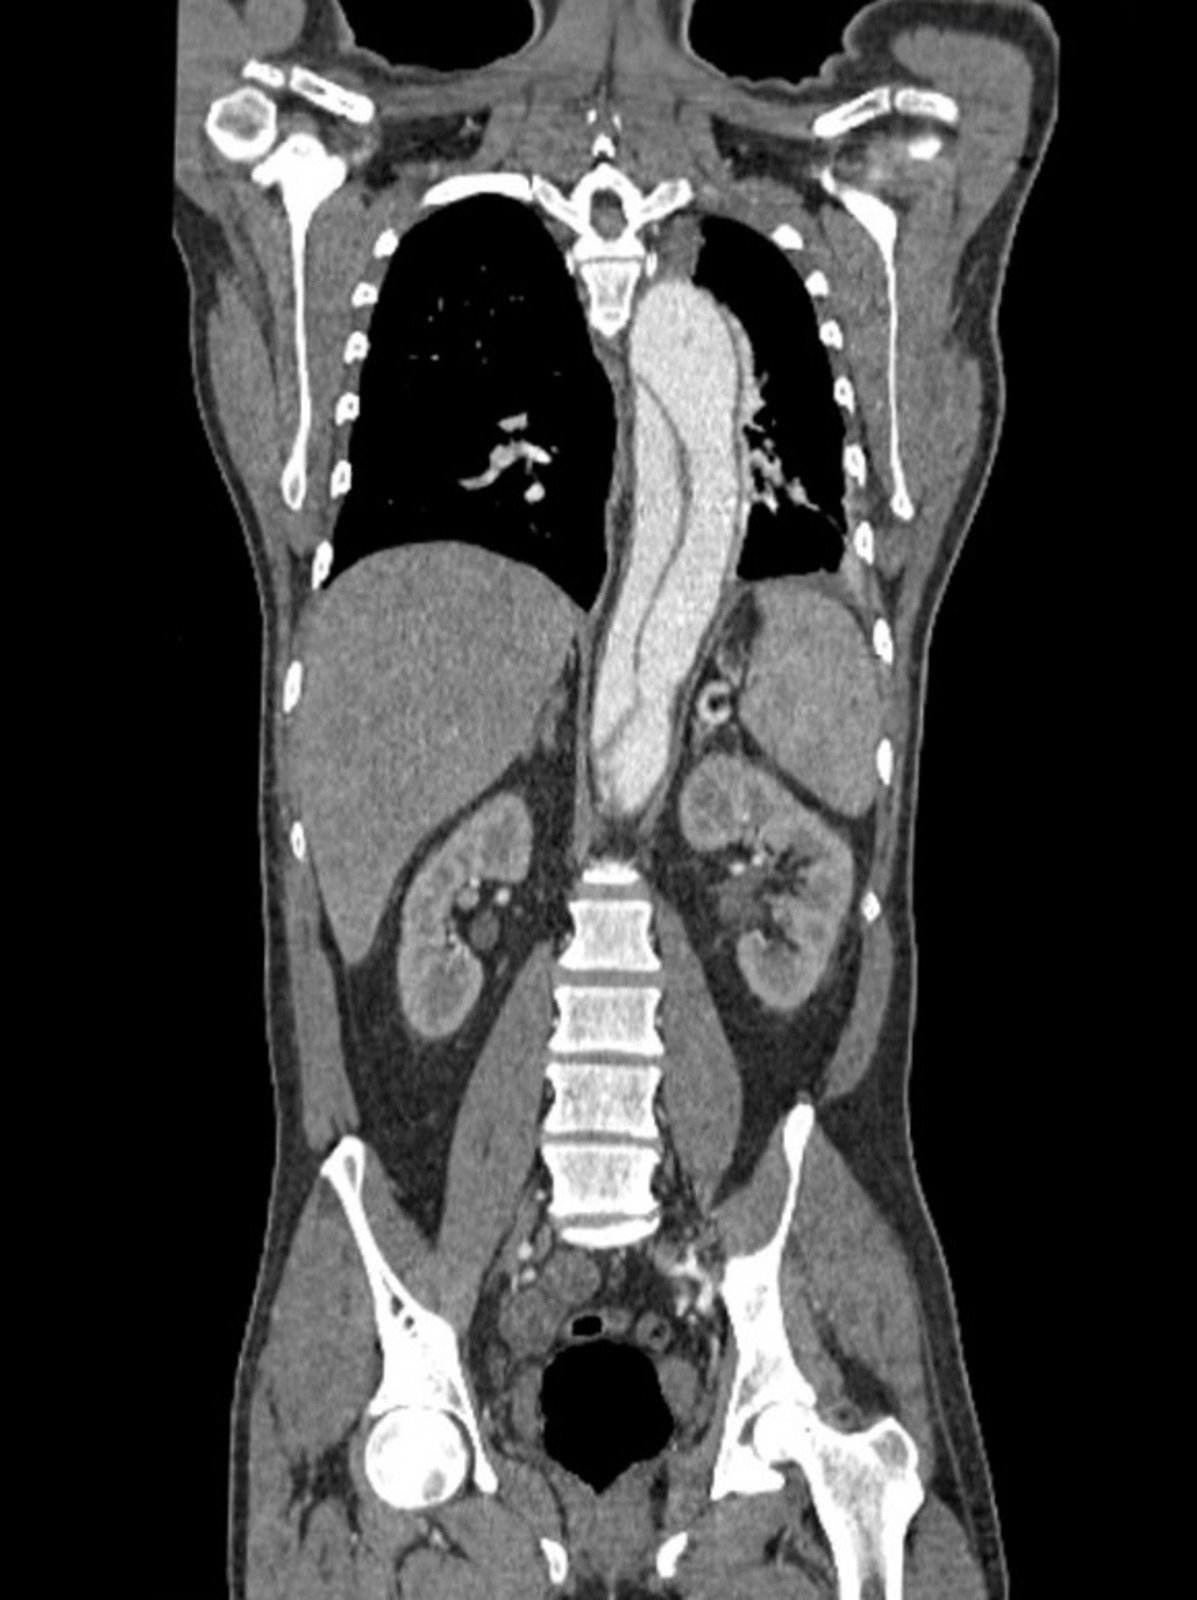

대동맥박리(Aortic dissection)는 대동맥 벽의 내막이 찢어지면서 혈액이 층간으로 유입되어 대동맥 벽을 두 층으로 분리시키는 심각한 상태입니다.

CT 스캔: 대동맥 박리를 시각적으로 확인할 수 있는 가장 일반적인 방법입니다.

대동맥박리(Aortic dissection)는 대동맥의 내벽이 찢어지면서 혈액이 내벽과 외벽 사이로 유입되어 층간을 분리시키는 상태입니다. 이는 매우 심각한 응급 상황으로, 신속한 진단과 치료가 필요합니다.

CT 스캔: 대동맥 박리를 시각적으로 확인할 수 있습니다.